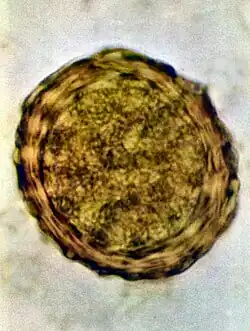

Ovos

Os ovos tem a princípio cor branca, mas devido ao contato com os pigmentos biliares das fezes, adquirem um tom castanho, às vezes descrito como de amarelo-escuro a marrom.[9] Tem formato oval a redondo e medem 45 a 75 micrômetros (μm) de comprimento e 35 a 45 (ou 50, a depender da fonte)[10] μm de largura;[11] possuem uma cápsula espessa graças a membrana externa mamilonada, formada por mucopolissacarídeos e secretada pela parede uterina. Internamente a esta membrana, existe outra constituída de quitina e proteína. A mais interna é delgada e impermeável à água constituída de 25% de proteínas e 75% de lipídios. É a camada mais interna que garante ao ovo a capacidade de resistir às condições adversas do ambiente. Em seu interior, os ovos tem uma massa de células germinativas. É possível encontrar nas fezes humanas ovos inférteis de áscaris, isso ocorre quando a fêmea do verme não foi inseminada, ou quando está iniciando a oviposição.[10] Pode-se identificar ao microscópio esse tipo de ovo pois eles possuem o interior desorganizado, com citoplasma granuloso e sem estruturas visíveis.[9][11] A membrana mamilonada é mais delgada e são mais alongados que os ovos férteis, medindo 80 a 90 μm de comprimento. Algumas vezes, mesmo os ovos férteis podem não ter a membrana mamilonada, sendo chamados de ovos decorticados.[9]